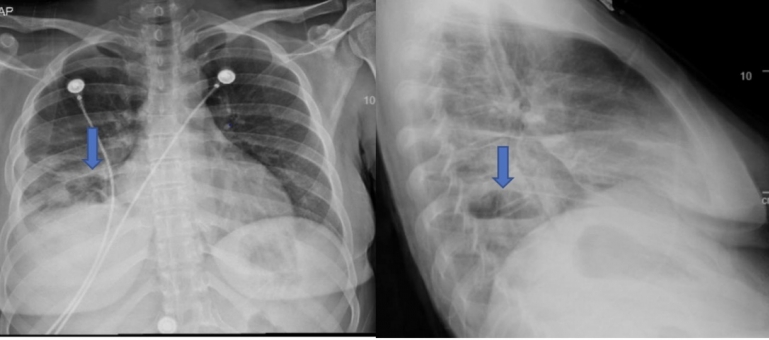

Answer: Cavitary lesion with air-fluid level consistent with abscess from septic emboli secondary to infective endocarditis

Or viewed on CT